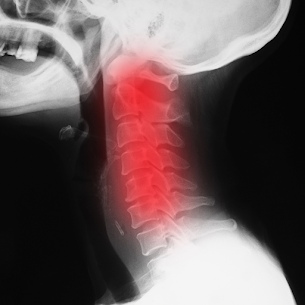

ストレートネック(スマホ首)について

【ストレートネック(スマホ首)】 首や肩、背中の痛みはストレートネックが要因かもしれません 現代病と言われるストレートネックとなる原因に、スマホの使いすぎやPCデスクワーク、巻き肩や猫背などがあります。 酷くなると頭痛や眩暈、吐き気、肩こり、腕の痺れや冷えなど代謝不全の症状が出現します。 ストレートネックの治療としては、首や肩甲骨の機能を取り戻す整体、肩甲骨運動やストレッチ、上半身の整いに対し下半身の支えが不安定であれば骨盤まわりをアプローチします。 もし頭痛その他お悩みの症状がストレートネックからではないか..と思った方がいましたら 実籾まりも整骨院までご相談ください!